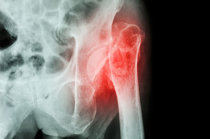

As causas mais comuns de dores nos quadris são as fraturas, que se tornam mais frequentes à medida que envelhecemos, pois as pessoas com osteoporose9 são especialmente susceptíveis a fraturar um osso, às vezes mesmo durante atividades rotineiras simples.

A evolução da dor no quadril depende, evidentemente, da sua causa e em geral tem o mesmo curso que elas. Se a causa for uma fratura18 no quadril, a mais comum, isso pode mudar significativamente a qualidade de vida da pessoa. Menos da metade das pessoas que sofreram fratura18 no quadril voltam à sua atividade anterior. Além disso, uma fratura18 no quadril pode ser seguida por muitas complicações, com risco de morte.